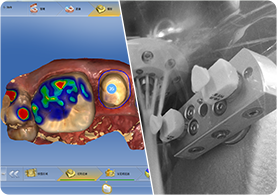

053D數碼口掃

06數字化設計與切削

新(xīn)橋口腔仿真修複含牙貼面、全瓷冠、嵌體(tǐ)仿真修複等。通過融合DSD美學(xué) 設計、顔面設計、紅白美學(xué)等牙科(kē)美學(xué)理(lǐ)念,結合牙科(kē)技(jì )術,結合牙齒形态、色澤、功能(néng)進行綜合設計,重塑完美笑線(xiàn)。其擁有(yǒu)的加工(gōng)站配備數字化修複設備,實現 椅旁修複的醫(yī)技(jì )患配合模式,縮短了修複時間,從取像,到設計,再到研磨完成,可(kě)讓顧客患者全程可(kě)視、親自參與到修複方案定制。